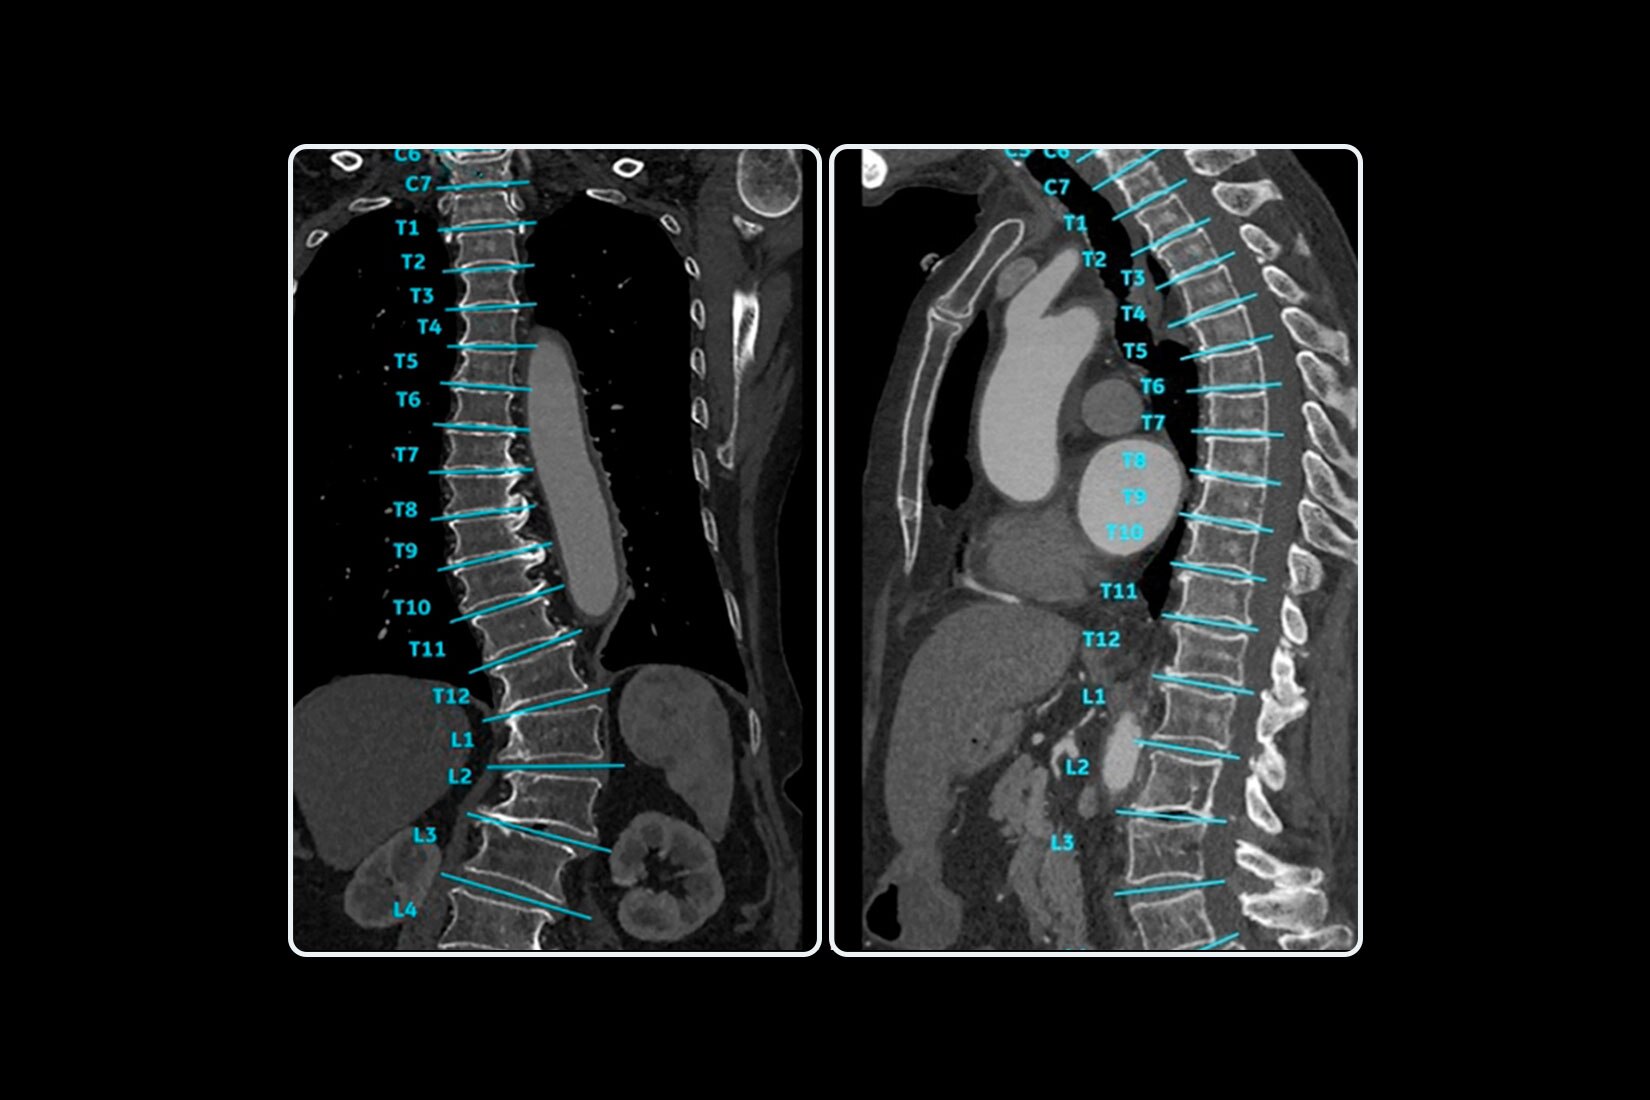

Automatic generation of consistent, anatomically relevant reformats.

- • Deep learning algorithm for automatic labeling of vertebral bodies and disc

spaces with >90% labeling accuracy

- • Deep learning algorithm for axial oblique images optimized for orientation

through vertebral disc spaces with >90% accuracy

- • Automatic generation of curved reformats to display the full spine in

aligned coronal/sagittal planes